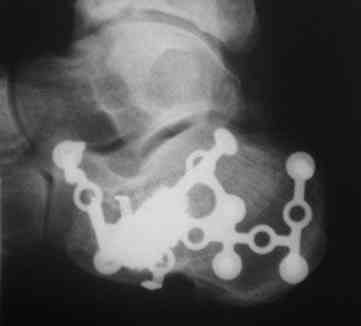

Re: перелом пяточной кости

послал Александр Кутков 06 Ноябрь 2010, 13:42

Из личного опыта, кстати после снятия кортикальной створки, репозицию удобно делать роторасширителем.